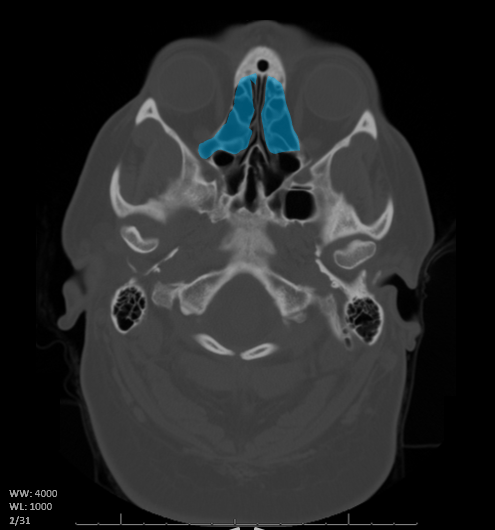

Name the structure/s highlighted blue in the CT image below.

What are the ethmoid sinuses?